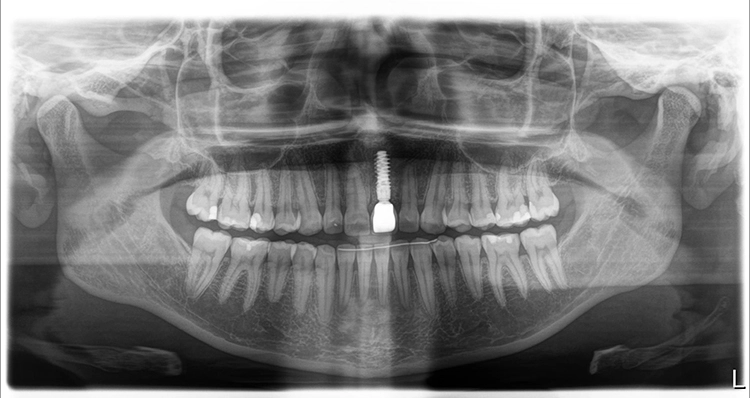

Die junge Patientin konsultierte die Zahnarztpraxis mit Beschwerden am Zahn 21. Der endodontisch vorbehandelte Zahn (multiple Wurzelspitzenresektionen) war mit einer Krone prothetisch versorgt (Abb. 1). Die Krone wirkte im Mund etwas dunkel und hatte einen grauen Schimmer. Da der Zahn zudem immer wieder Beschwerden bereitete, äußerte die Patientin den Wunsch nach einer Neuversorgung. Ansonsten war sie vollbezahnt und funktionell ohne pathologischen Befund. Parodontal zeigte sich eine kleine Rezession im Unterkiefer-Frontzahnbereich.

Zu den schwierigen Anforderungen im Frontzahnbereich gesellten sich hohe ästhetische Ansprüche. Die klinische sowie radiologische Diagnostik (Abb. 2) ergaben, dass der Versuch des Erhalts von Zahn 21 keine sichere Perspektive bot. Die Entscheidung fiel für die Extraktion des Zahnes. Um das Hart- und Weichgewebe bestmöglich vor der physiologischen Remodellierung nach der Extraktion zu bewahren, wurde eine Sofortimplantation geplant.